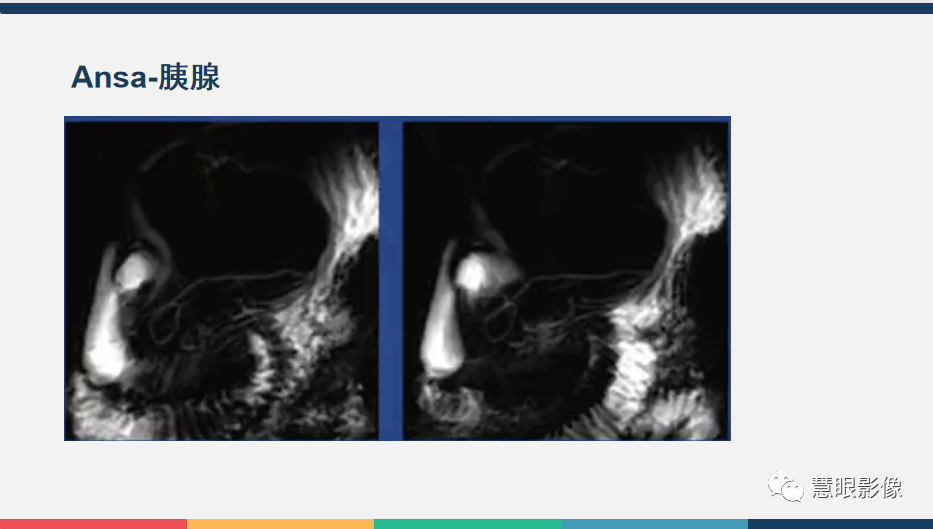

【PPT】胰腺解剖变异、发育异常及相关病变影像评估-1